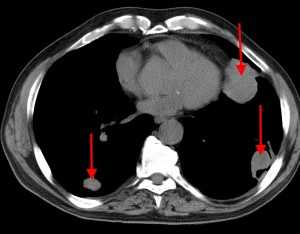

КТ: метастазы в легких при раке молочной железы. На изображении справа красной звездочкой отмечен опухолевый узел в молочной железе, красными стрелками - область прорастания опухоли в грудную стенку. Синими звездочками отмечен карциноматозный плеврит — скопление жидкости в плевральной полости. Слева стрелкой отмечен вторичный узел.

Опухоль левого легкого с частичным некрозом и деструкцией ребер. Визуализируются два метастаза в подключичных лимфоузлах и в мышцах (стрелки), которые на КТ не видны. Необходимо выполнить трансторакальную биопсию той части опухоли, которая расположена в периферических отделах, чтобы получить образец жизнеспособных тканей.